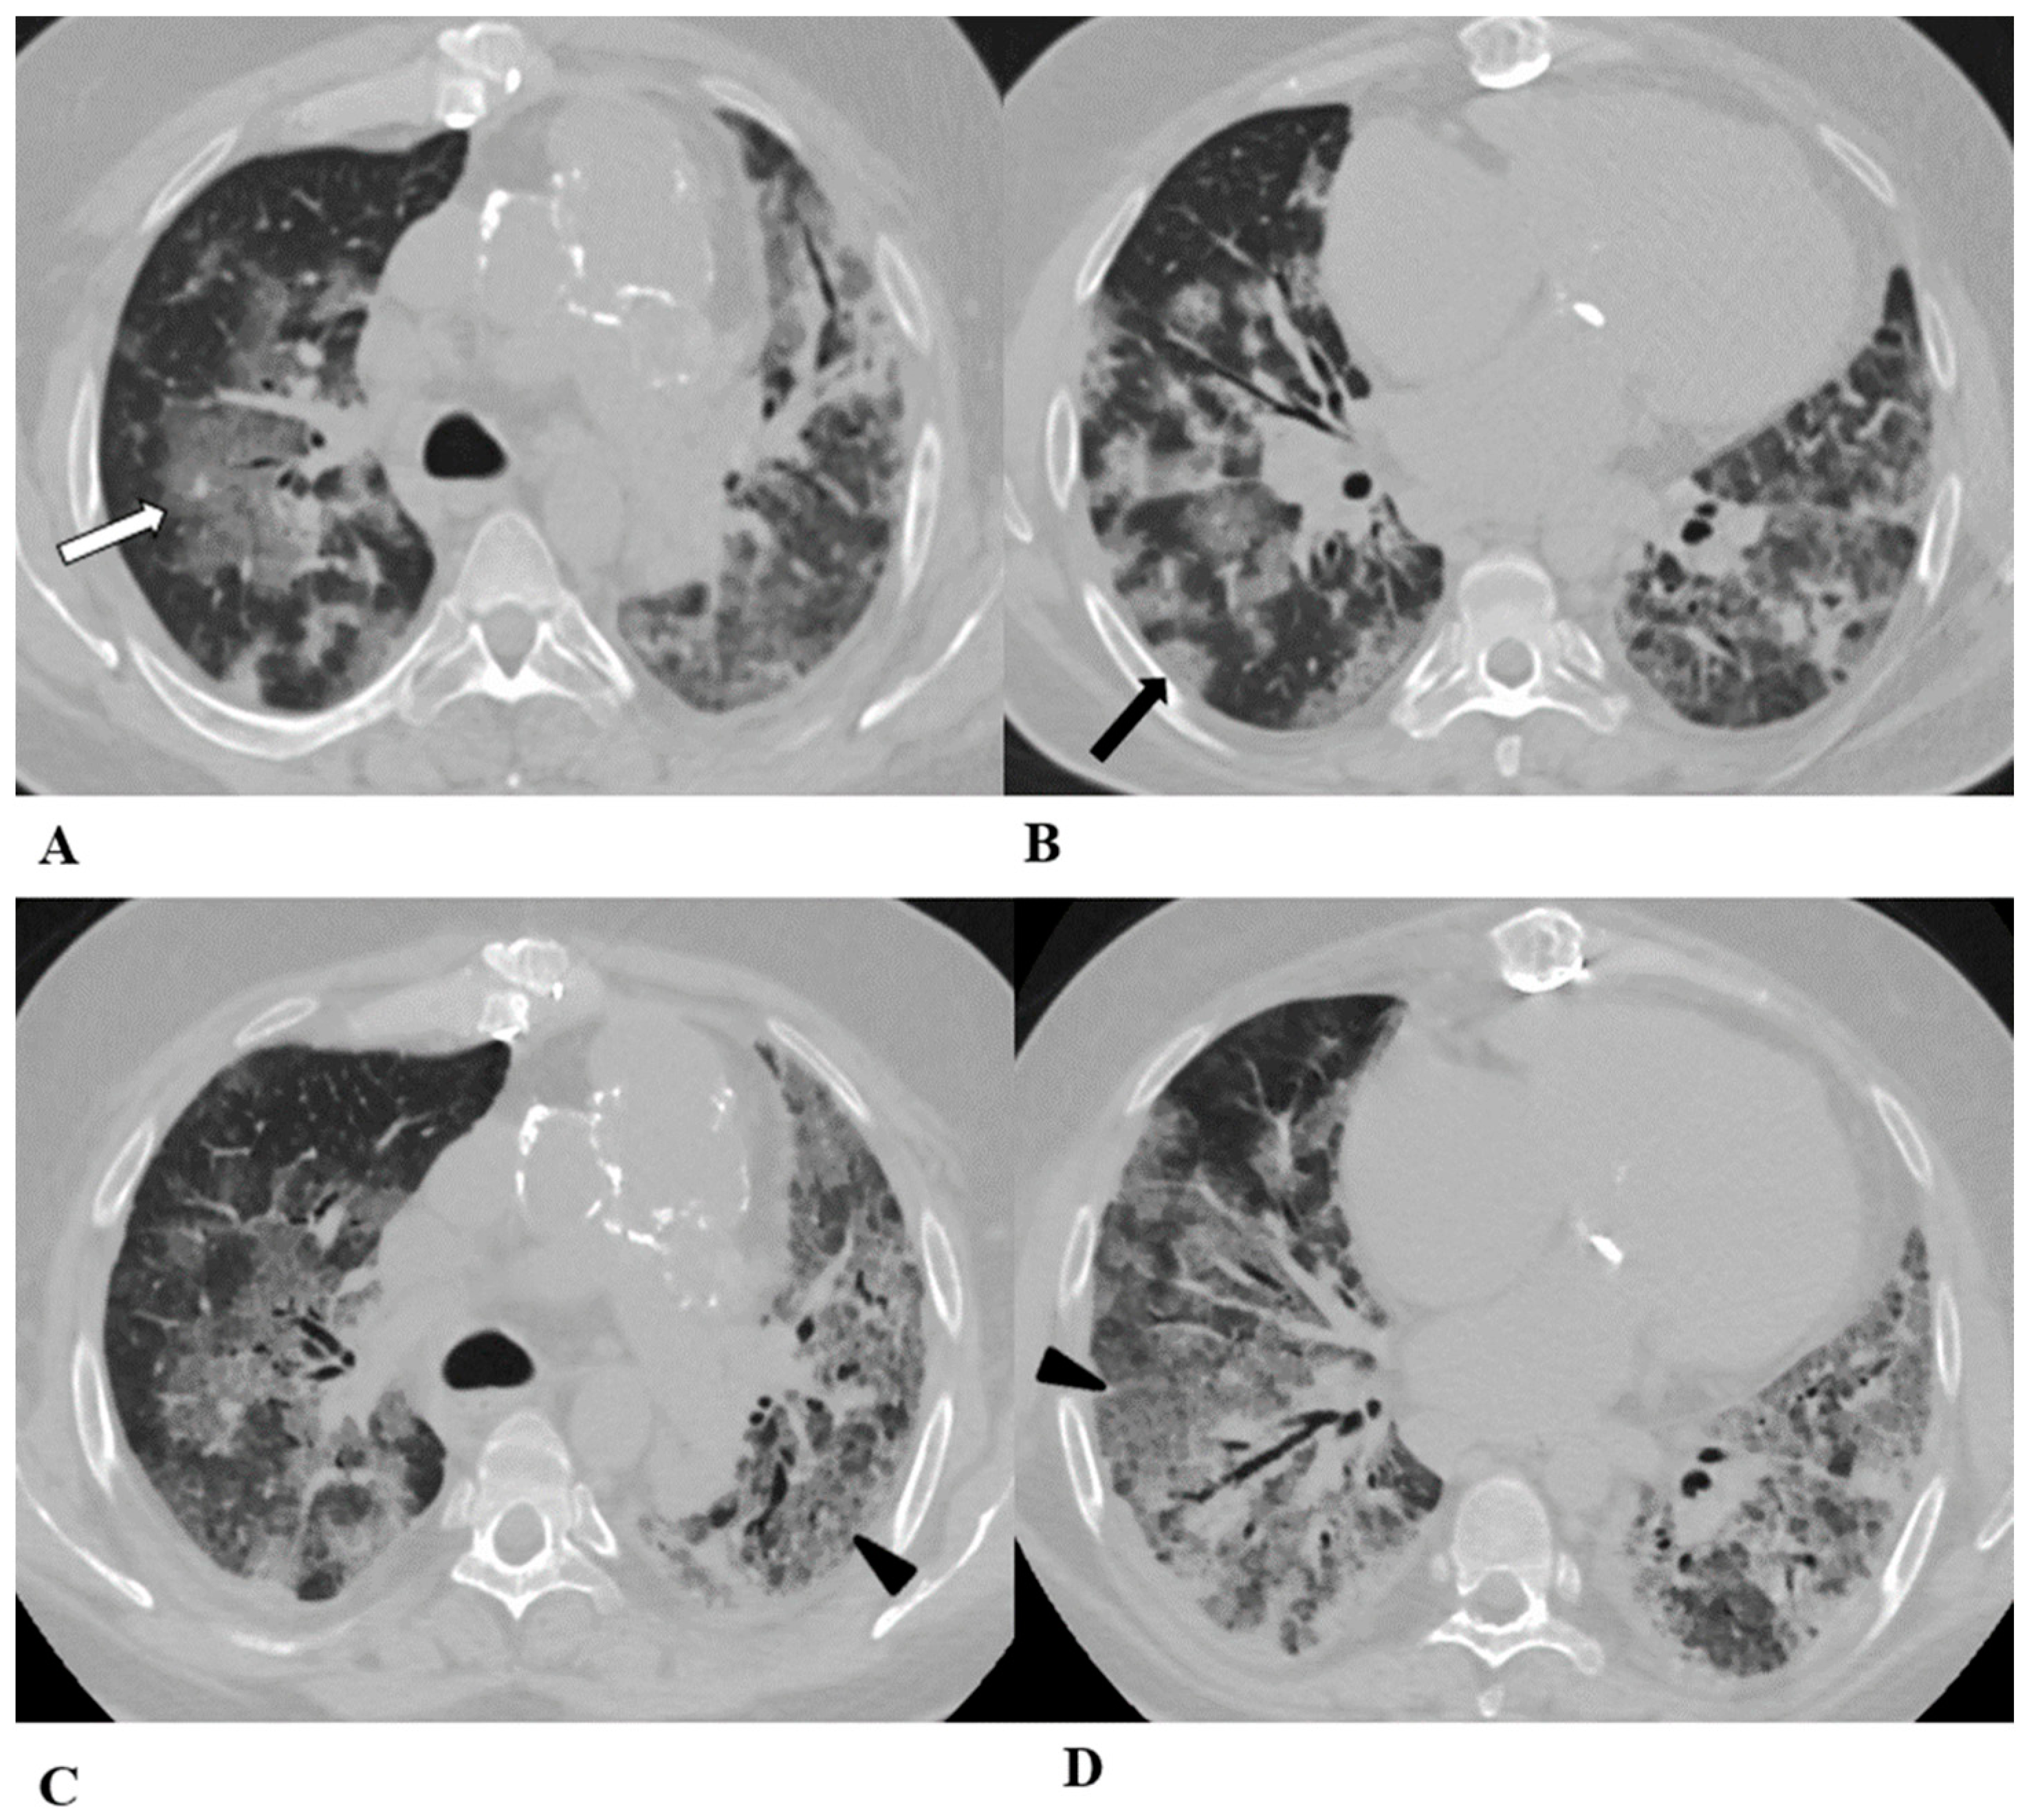

Figure 4.

Acute interstitial pneumonia (AIP)/acute respiratory distress syndrome (ARDS). Acute interstitial pneumonia (AIP) and acute respiratory distress syndrome (ARDS) can be a consequence of both pathogenic intrapulmonary and extrapulmonary stimuli. They are clinically characterized by acute respiratory failure, a consequence of alveolar thickening due to hyaline membrane deposition and inflammatory cells’ infiltration. Both conditions likely represent the same pathology, with AIP probably accounting for some of the idiopathic cases of ARDS.

ARDS from extrapulmonary disease shows bilateral symmetrical changes on CT, whereas in pulmonary ARDS, the opacities tend to be asymmetrical.

The initial form of ARDS can also be classified as diffuse alveolar damage (DAD), followed by the organizing and delayed phases.

HRCT features depend on the phase of the disease, with the possibility of GGOs in the acute phase, and lung cysts and pulmonary opacifications often with an anteroposterior gradient in the delayed phase; complete resolution or evolution into a coarse reticular pattern, traction bronchiectasis and possible bullae, as result of prolonged ventilation, may be found. Sometimes, pleural effusion is observed [9,12,16].

(A–D) A 45-year-old man with rectal carcinoma metastatic to the liver, treated with pembrolizumab. After nearly three months of immunotherapy, the patient suffered acute respiratory failure and interstitial pneumonia suggestive of ARDS in the clinical setting.

Baseline axial chest CT scans (A,B) showed numerous partially confluent areas of GGO, more represented in the perihilar regions as a result of extensive alveolar damage (white arrow), with some dependent asymmetrical peripheral consolidations (black arrow) like an early ARDS pattern, which made it necessary to hospitalize the patient in the intensive respiratory care unit with nose–tracheal intubation.

Three weeks later, CT images (C,D) demonstrated lung architecture disruption, a large component of GGO, reticulation with areas of crazy-paving (black arrowheads), incremented consolidation in the dependent lung and traction bronchiectasis, as seen in the delayed fibrotic ARDS phase.

As accessory findings, note the altered profile of the right ventricle outflow tract (RVOT) and pulmonary trunk with wall calcifications, as a result of multiple reconstructive operations in pediatric age for tetralogy of Fallot.